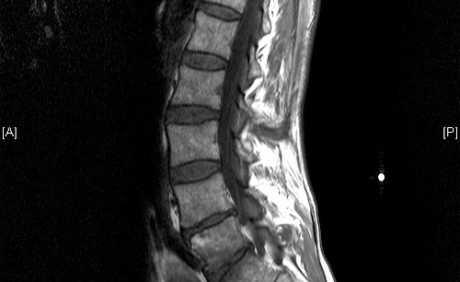

Hernija diska

Kada bismo slučajnim odabirom s Korza uzeli sto punoljetnih šetača i podvrgli ih MR dijagnostici, kod više od polovice pronašli bi barem jedan deformiran disk u smislu hernije